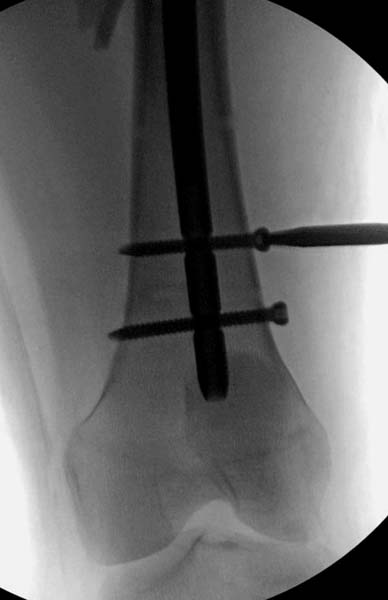

Около 11.00 вечера больная переведена в реанимацию, без сознания, но стабильная.. На третьий день провели стабилизацию перелома бедра антеградным остеосинтезом.

Закрытый БИОС решает множественные проблемы связанные с лечением переломов, но проблема дистальной блокировки без рентгена до сих пор остается нерешенной. Рекламированные производителями приспособления для дистальной блокировки из-за различной кривизны кости не эффективны или стоит очень дорого (Smith&Nephew SureLock). Задержка операции из-за блокировки не всегда удовлетворяет, и многих вынуждает искать альтернативные методы фиксации. С результатами таких действий, остеомиелитом и несращениями, встречаемся в ежедневной жизни..

Для решения проблемы дистальной блокировки компания DigiMed недавно предложила систему блокировки без рентгена. Пока в стране только два набора и только для антеградных гвоздей, но компания работает над созданием устроиства для других гвоздей тоже..

Результат первых случаев показала отсутствие разницы между занятиями на муляжах, а также Workshop и с удивительной точностью вывел латерально над кожей специальное сверло. Дальше по сверлу тонкий направитель и проводится сверление каннюлированным сверлом....